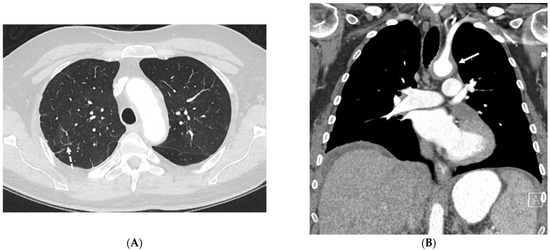

5.1. Invasive Lung Adenocarcinoma

5.2. Kaposi’s Sarcoma

5.3. Lymphoma

5.4. Leukemia